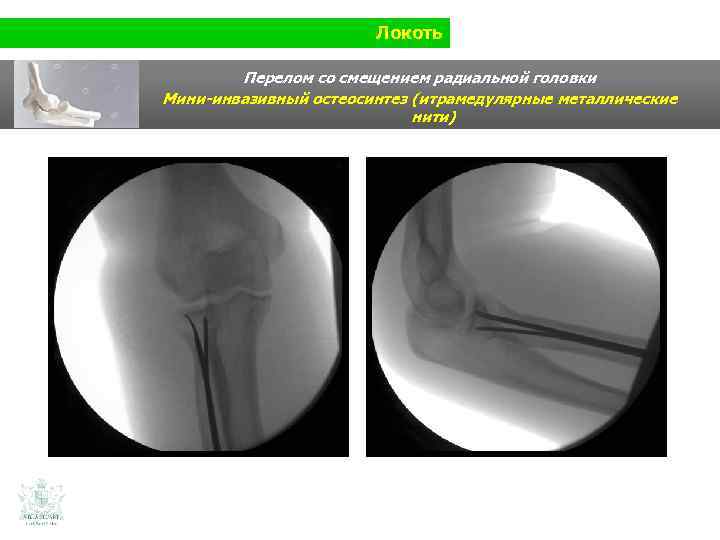

Локоть Перелом со смещением радиальной головки

Локоть Перелом со смещением радиальной головки Мини-инвазивный остеосинтез (итрамедулярные металлические нити)